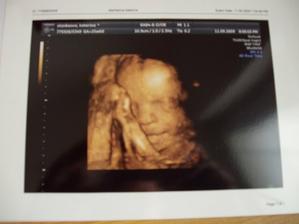

11.9.09 3D UTZ potvrzeni holciciky (amálka)